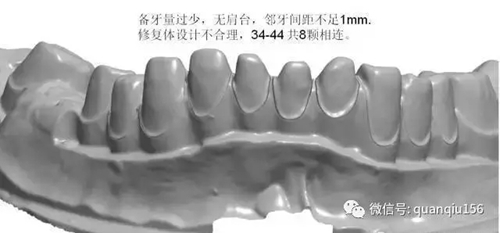

1、臨床備牙不合理或基牙條件不適合做氧化鋯

如:無肩臺、凹面肩臺、邊緣線不清晰、雙重邊緣線、備牙空間不足、基牙有倒凹或牙橋沒有共同就位道、基牙切端或頜緣過于尖銳等等。